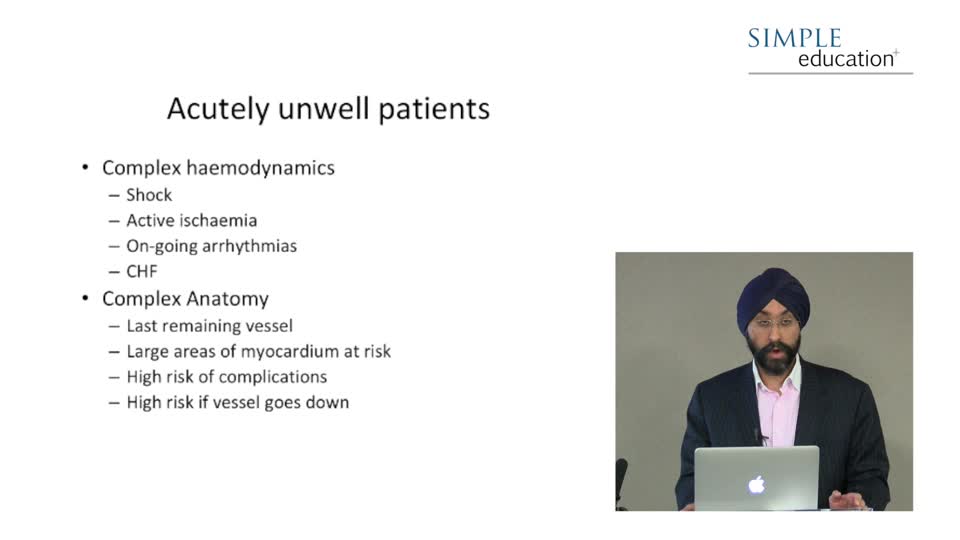

Fail Safe Guide to Access Routes and Guide Catheters in Acutely Unwell Patients - Dr. Amarjit Sethi